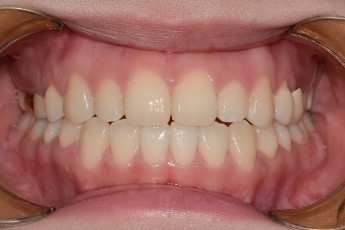

Before

After